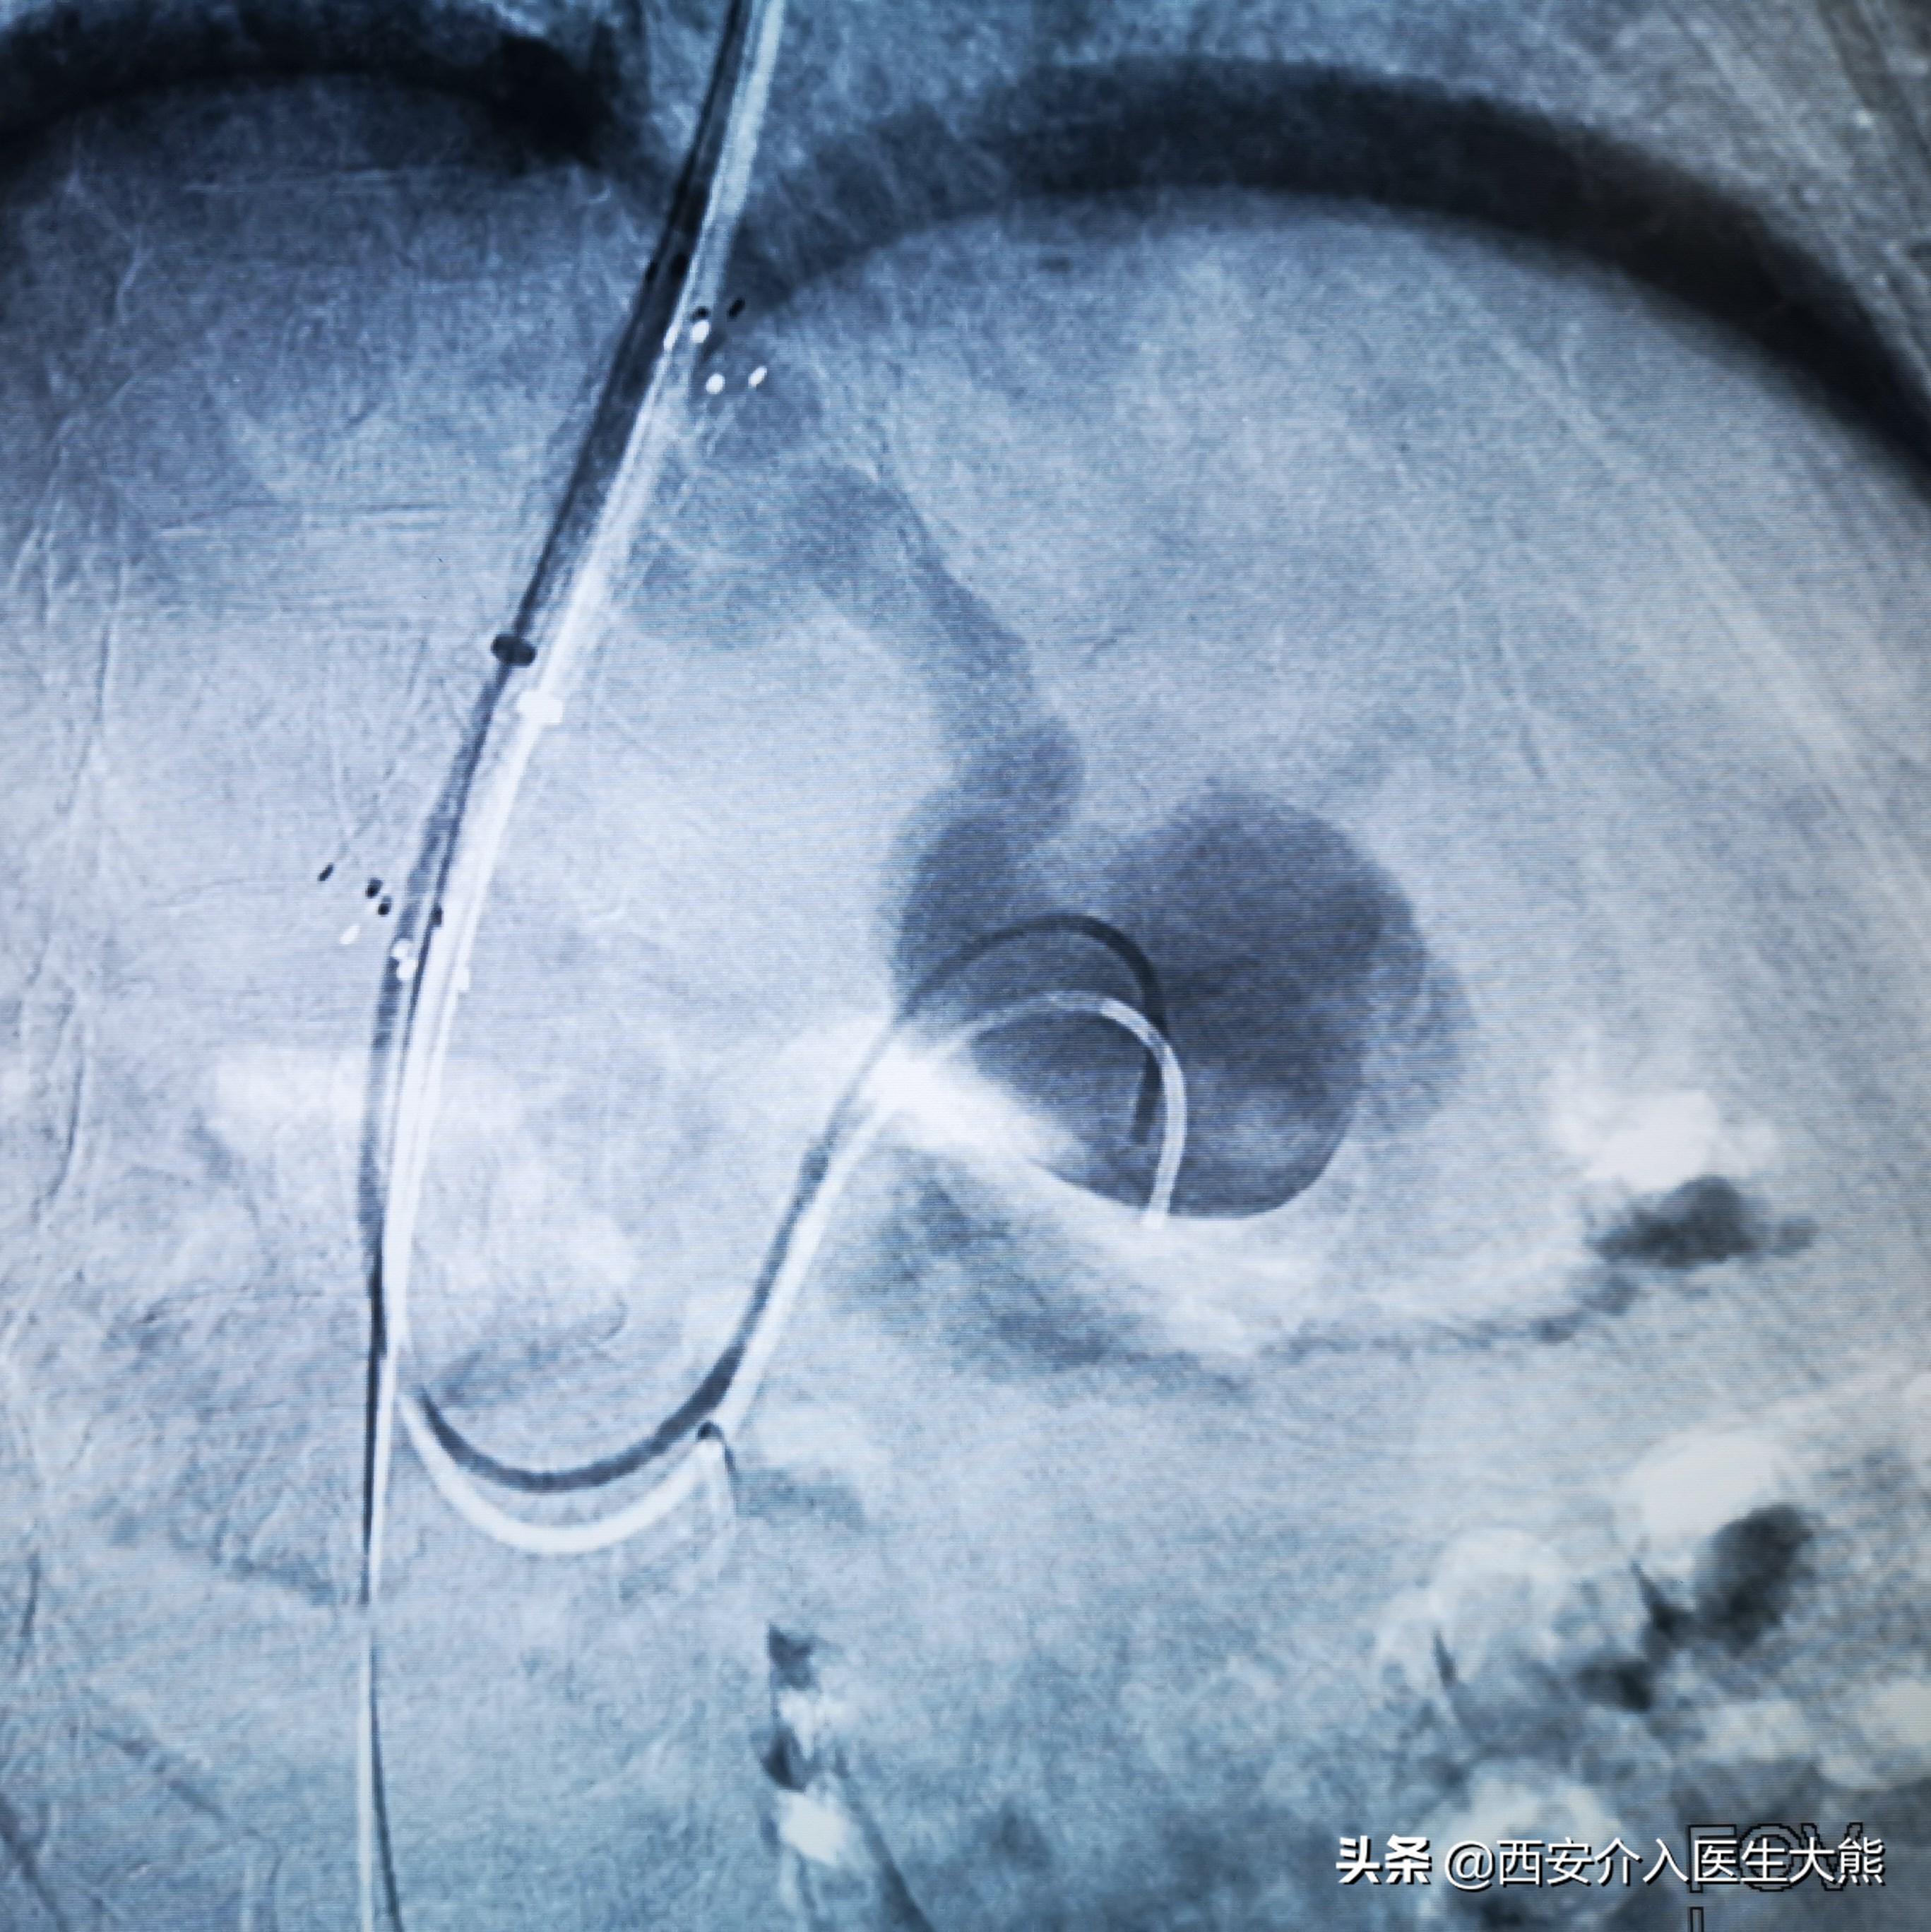

3.术中DSA:

扩张的脐静脉

扩张的没静脉和胃冠状静脉

扩张的胃冠状静脉

TIPS和食管胃底静脉栓塞术后

这名患者的治疗过程就符合该治疗策略。术前的CT平扫已经显示极度扩张的胃冠状静脉,这在DSA影像上得到证实。2018年患者第二次出血时做的增强CT上已经显示出患者的胃冠状静脉扩张。此时,已经具有行TIPS的指征。在经过3年的变化后,病情是急剧加重。如果出血剧烈、生命体征不平稳,或各种原因导致不能行急诊胃镜的情况下,不要错过TIPS降低门脉压力的机会。